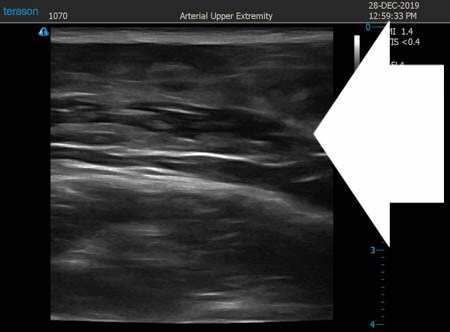

いつものように3Dタッチビュー(超音波)で

皮下脂肪層を評価してみましょう。

左肩甲骨横